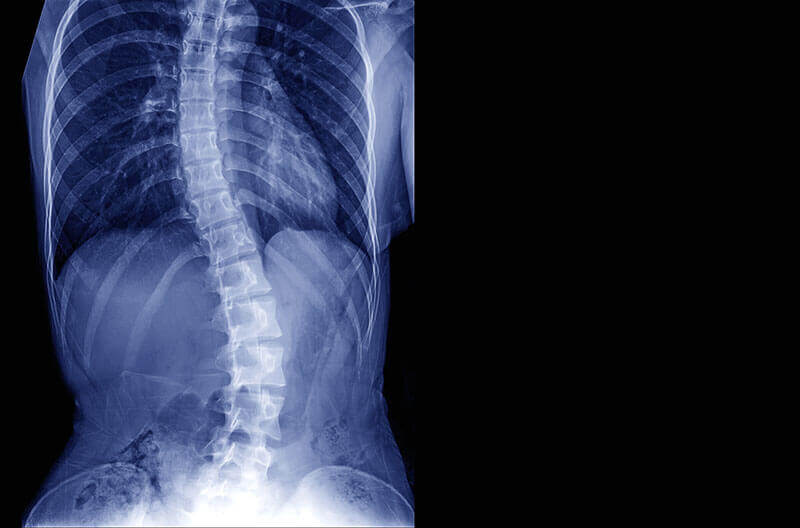

Radiografia este principalul obiect in imagistica scoliozelor, atat pentru a confirma diagnosticul, cat si pentru a exclude orice conditii de baza. Desi este definita ca o deformare laterala aceasta este o deformitate de rotatie tridimensionala (3D). Indicarile pentru radiografie includ modificari ale alinierii normale a coloanei vertebrale pe examinarea fizica, evaluarea progresiei curburii spinale si urmarirea tratamentului. Pentru studiul scoliozelor, metoda preferata este o radiografie posteroanteriala cu pacientul in pozitie verticala.Pentru acei pacienti care sunt evaluati sau sunt tratati clinic pentru scolioza, alte imagini includ imagini de incovoiere drepte si stangi, o imagine laterala laterala a fasciculului si o imagine posteroanteriala a incheieturii mainii stangi pentru determinarea varstei osoase.

Analiza radiografica ar trebui sa identifice prezenta, directia, localizarea si varful curburii. Stabilirea maturitatii scheletice este importanta deoarece curbele scolitice usoare pana la moderate nu progreseaza dupa incetarea cresterii.

![Radiografie coloana vertebrala tipuri de scolioza]()